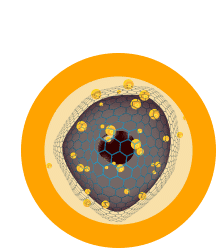

Step 3

The applicator supplies a sequence of short-duration electrical pulses through a series of needles.

Step 4

Electrical pulses result in increased permeability of the cell membrane, allowing DNA-based IL-12 to enter.